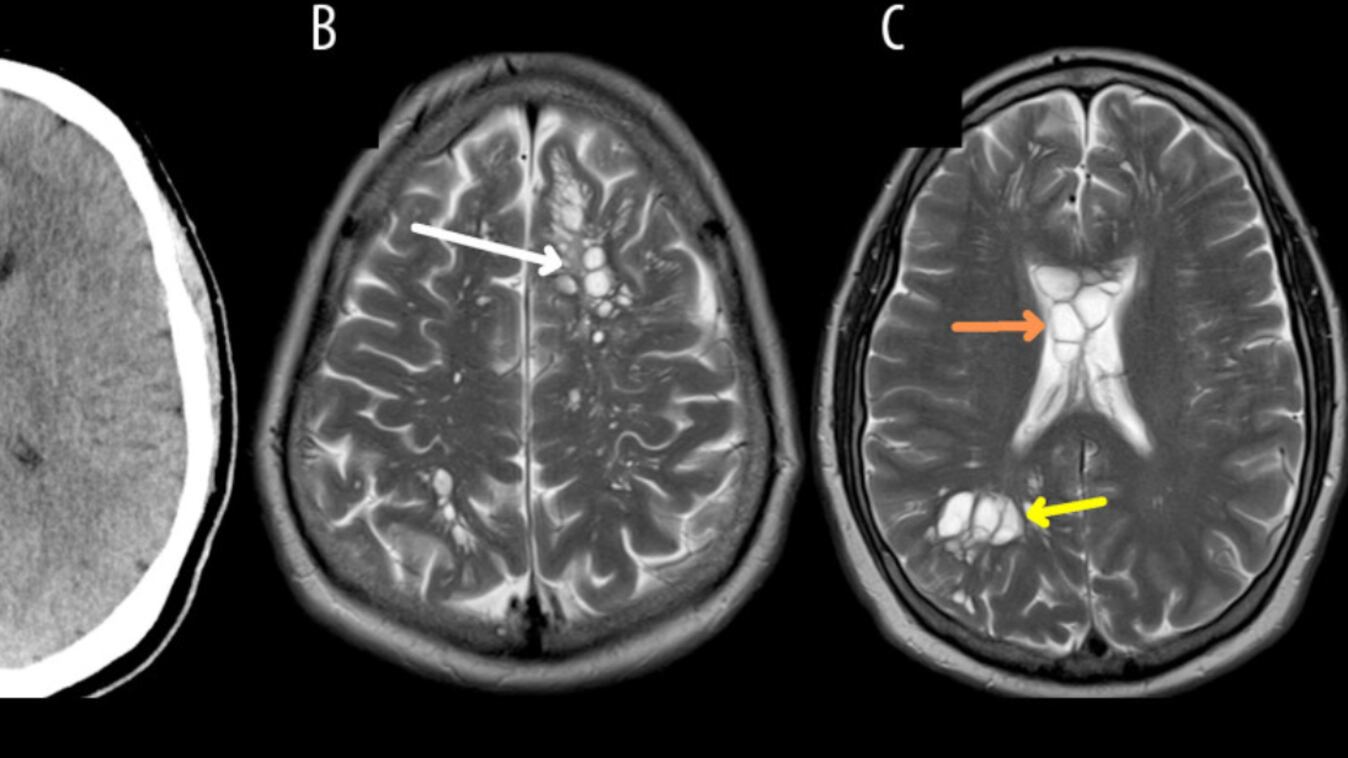

De acordo com o relatório da CNN, o médico fez uma tomografia que revelou múltiplos cistos em todo o cérebro. Diante da suspeita inicial de que poderia estar sofrendo de uma doença neurológica rara chamada cistos neurogliais congênitos, os médicos o internaram em um hospital de Orlando para consultar com neurocirurgia.

E bem, os exames realizados revelaram que os cistos eram larvas que se instalaram no cérebro e causaram uma infecção chamada neurocisticercose.